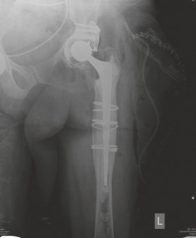

Initial radiographic evaluation consisted of standardized, weight-bearing anteroposterior (AP) and lateral views of the right hip, alongside a full-length AP pelvis radiograph to assess bilateral symmetry, pelvic obliquity, and offset.

The AP Pelvis radiograph demonstrated catastrophic failure of the index arthroplasty. There was evidence of severe, expansile acetabular osteolysis, predominantly localizing to DeLee and Charnley zones 1 (superior) and 2 (medial). The uncemented acetabular shell exhibited significant superior and medial migration, with apparent protrusion of the medial wall into the true pelvis. A continuous, wide radiolucent line (>2 mm) was visible at the bone-prosthesis interface, confirming gross aseptic loosening. The teardrop was obliterated, and the Kohler's line (ilioischial line) appeared compromised, raising the clinical suspicion for an uncontained medial defect or impending pelvic discontinuity.

The lateral radiograph corroborated the AP findings, further delineating the extent of anterior and posterior column involvement. The femoral component also exhibited unequivocal signs of failure. Extensive radiolucency was evident at the bone-prosthesis interface spanning Gruen zones 1, 7, and 2, consistent with proximal osteolysis. Distally, in zones 3, 4, and 5, there was prominent cortical hypertrophy and pedestal formation at the tip of the stem. This radiographic pattern is pathognomonic for proximal stress shielding combined with distal point loading, indicating a loss of proximal fixation and subsequent micro-motion leading to distal toggle. Minor axial subsidence of the femoral stem (approximately 8 mm) was also noted when compared to immediate postoperative radiographs from 15 years prior.

Based on the comprehensive imaging suite, the acetabular defect was classified as a Paprosky Type IIIB. This classification signifies severe superior migration (>3 cm), massive volumetric bone loss, an incompetent superior dome, and a teardrop that is frequently destroyed or significantly altered, yet with the maintenance of pelvic continuity. The femoral defect was classified as a Paprosky Type III, characterized by extensive metadiaphyseal bone loss with intact diaphyseal bone distal to the isthmus, capable of providing initial mechanical stability for a revision stem.

Clinical & Radiographic Imaging